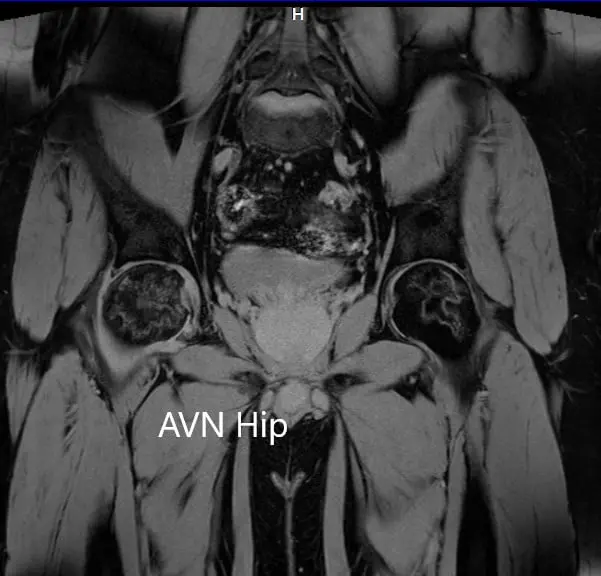

T2WI coronal section of MRI showing AVN hip.

Hypointense areas were present on both T1WI and T2WI on both the head of the femur suggestive of sclerosis. Surrounding bone marrow edema was present and the bilateral necrotic area was approximately 70%.